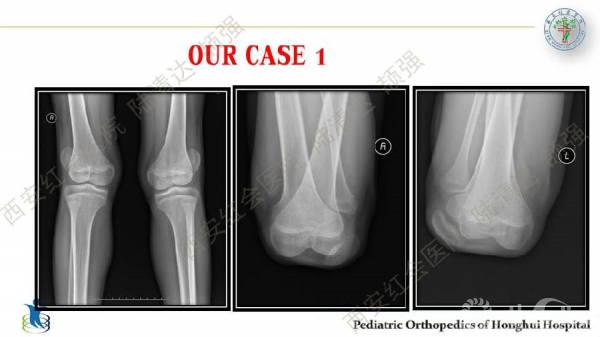

儿童习惯性髌骨脱位

习惯性髌骨脱位,多见于儿童,女性多于男性。临床表现主要为行走步态难看、下肢无力、易摔跤等,而反复摔跤的病史常是患者就诊的主诉。其病理特点主要膝关节内外侧伸肌肌群不平衡及局部结构发育异常,表现为:股外侧肌及膝外侧软组织挛缩,髌韧带附着点偏外,股内侧肌群萎缩无力及MPFL发育不良,髌股关节滑车发育不良及膝外翻畸形等。习惯性髌骨脱位的治疗,建议早发现早治疗。不仅能有效解决脱位问题,还可避免继发畸形。如治疗延误,可出现髋、膝关节继发屈曲、腰前凸加大等畸形。甚至膝关节骨性关节炎,影响工作与生活。